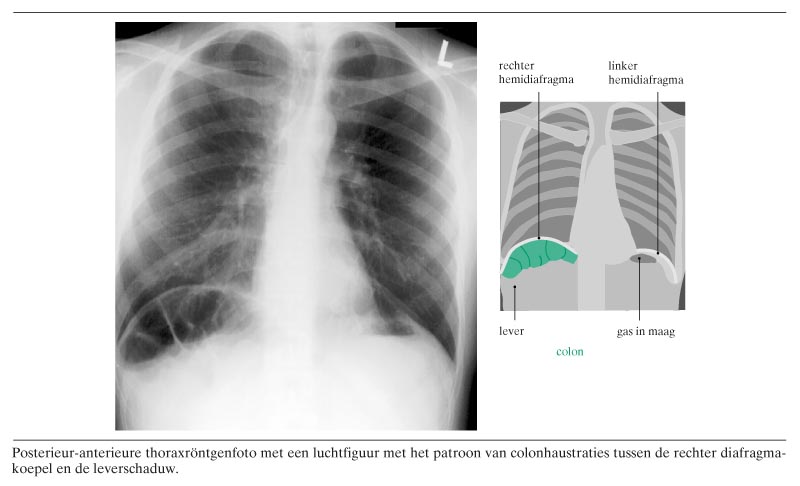

Een 27-jarige man kwam voor een thoraxfoto omdat hij sinds 3 maanden hoestte. Al jarenlang had hij veel diarree, al was het de laatste tijd wat minder. Zijn gewicht was constant. Op de thoraxfoto waren aan hart en longen geen afwijkingen te zien. Wel was er een luchtfiguur onder de rechter diafragmakoepel (figuur). Normaal gesproken behoort hier alleen de leverschaduw zichtbaar te zijn. Bij deze patiënt was deze luchtfiguur het gevolg van interpositie van de flexura coli dextra tussen de lever en het diafragma. Deze hepatodiafragmatische interpositie is voor het eerst beschreven in 1899 en staat sinds…